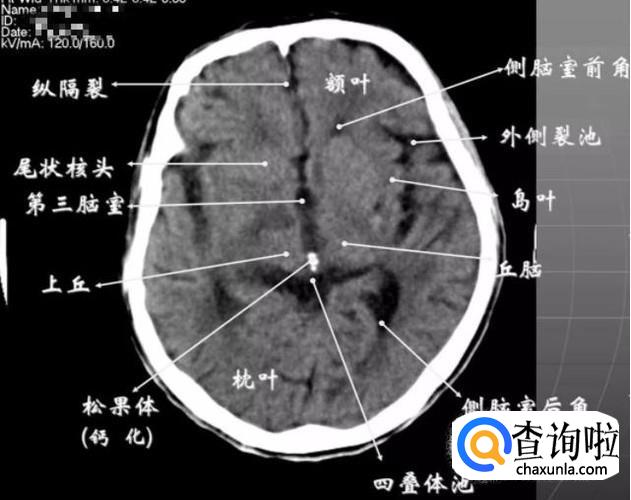

第三脑室下部层面

① 显示侧脑室前角的下部:前方---额叶;外侧---尾状核头部;后方中线处---第三脑室,其两侧连接丘脑。

② 颅后窝:“Y”字形或“V”字形的小脑幕,幕下结构在内侧(小脑上蚓部),幕上结构在外侧(枕叶)。

③ 四叠体池:位于小脑蚓部前方。

- 012

第三脑室上部层面

① 基底核、丘脑。

② 内囊前脚(前肢);尾状核和豆状核之间。

③ 内囊膝部和后脚(后肢):位于豆状核(由外侧的壳核和内侧的苍白球组成)及丘脑之间。

④ 壳核的外侧:外囊、屏状核、最外囊、岛叶(脑岛)。

⑤ 四叠体池:两侧枕叶之间,池内有松果体,向前与第三脑室连接。